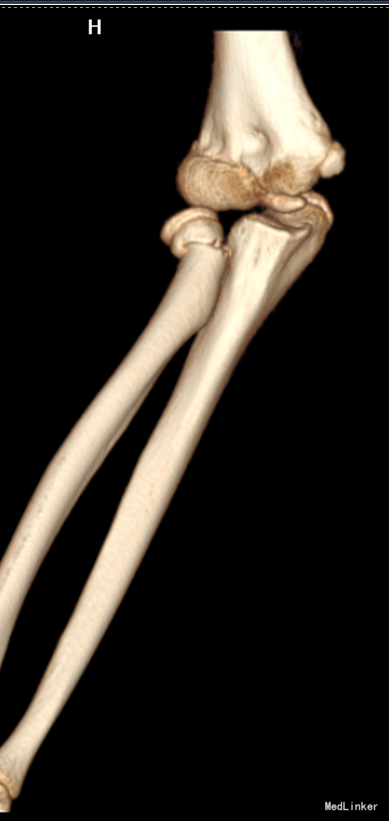

患者自述于2015年1月8日14时余不慎摔伤,右手伸直着地,感觉疼痛、肿胀,活动受限。遂急诊来我院,急诊给予行右肘关节三维CT检查,提示:右桡骨近端骨折。现为求进一步系统治疗送入我科,急诊以“右桡骨颈骨折”为主要诊断收入我科

专科查体:患者无明显外伤伤口,肘关节肿胀,右尺骨鹰嘴压痛(+),右桡骨小头处深压痛(+),肘关节活动受限,右上肢皮肤感觉无减退,桡动脉可扪及搏动,皮温正常,拇指背伸肌力正常。 辅助检查:我院右肘关节三维CT: 右桡骨近端骨折